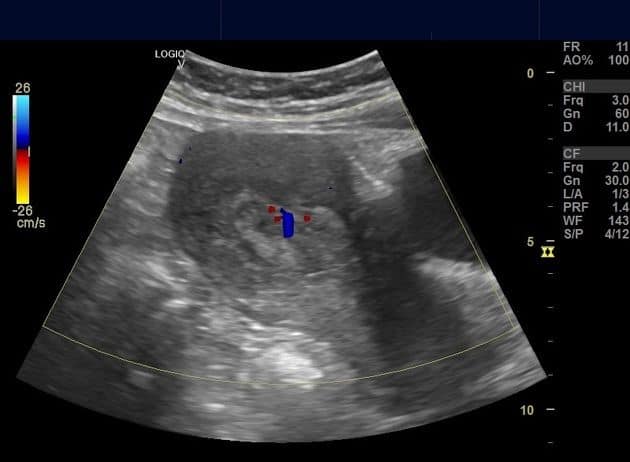

Polyp nội mạc tử cung

» Thông tin: Nữ giới – 40 tuổi.

» Lâm sàng: Rong kinh.